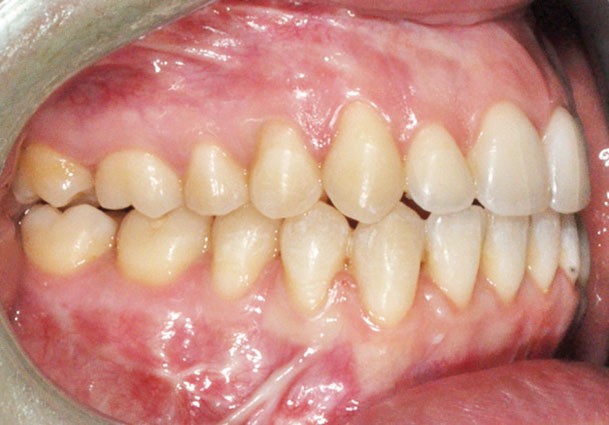

Distalisation molaire mandibulaire par corticotomies associées aux miniplaques (fig. 7)

Le recul molaire a apporté l’espace nécessaire à la correction de l’encombrement avec en plus un léger recul incisif qui a permis de positionner de façon idéale l’incisive dans la symphyse. Une distalisation des secteurs latéraux de 3 mm à droite et 2 mm à gauche permettant aussi de symétriser les relations molaires a donc été obtenue en…